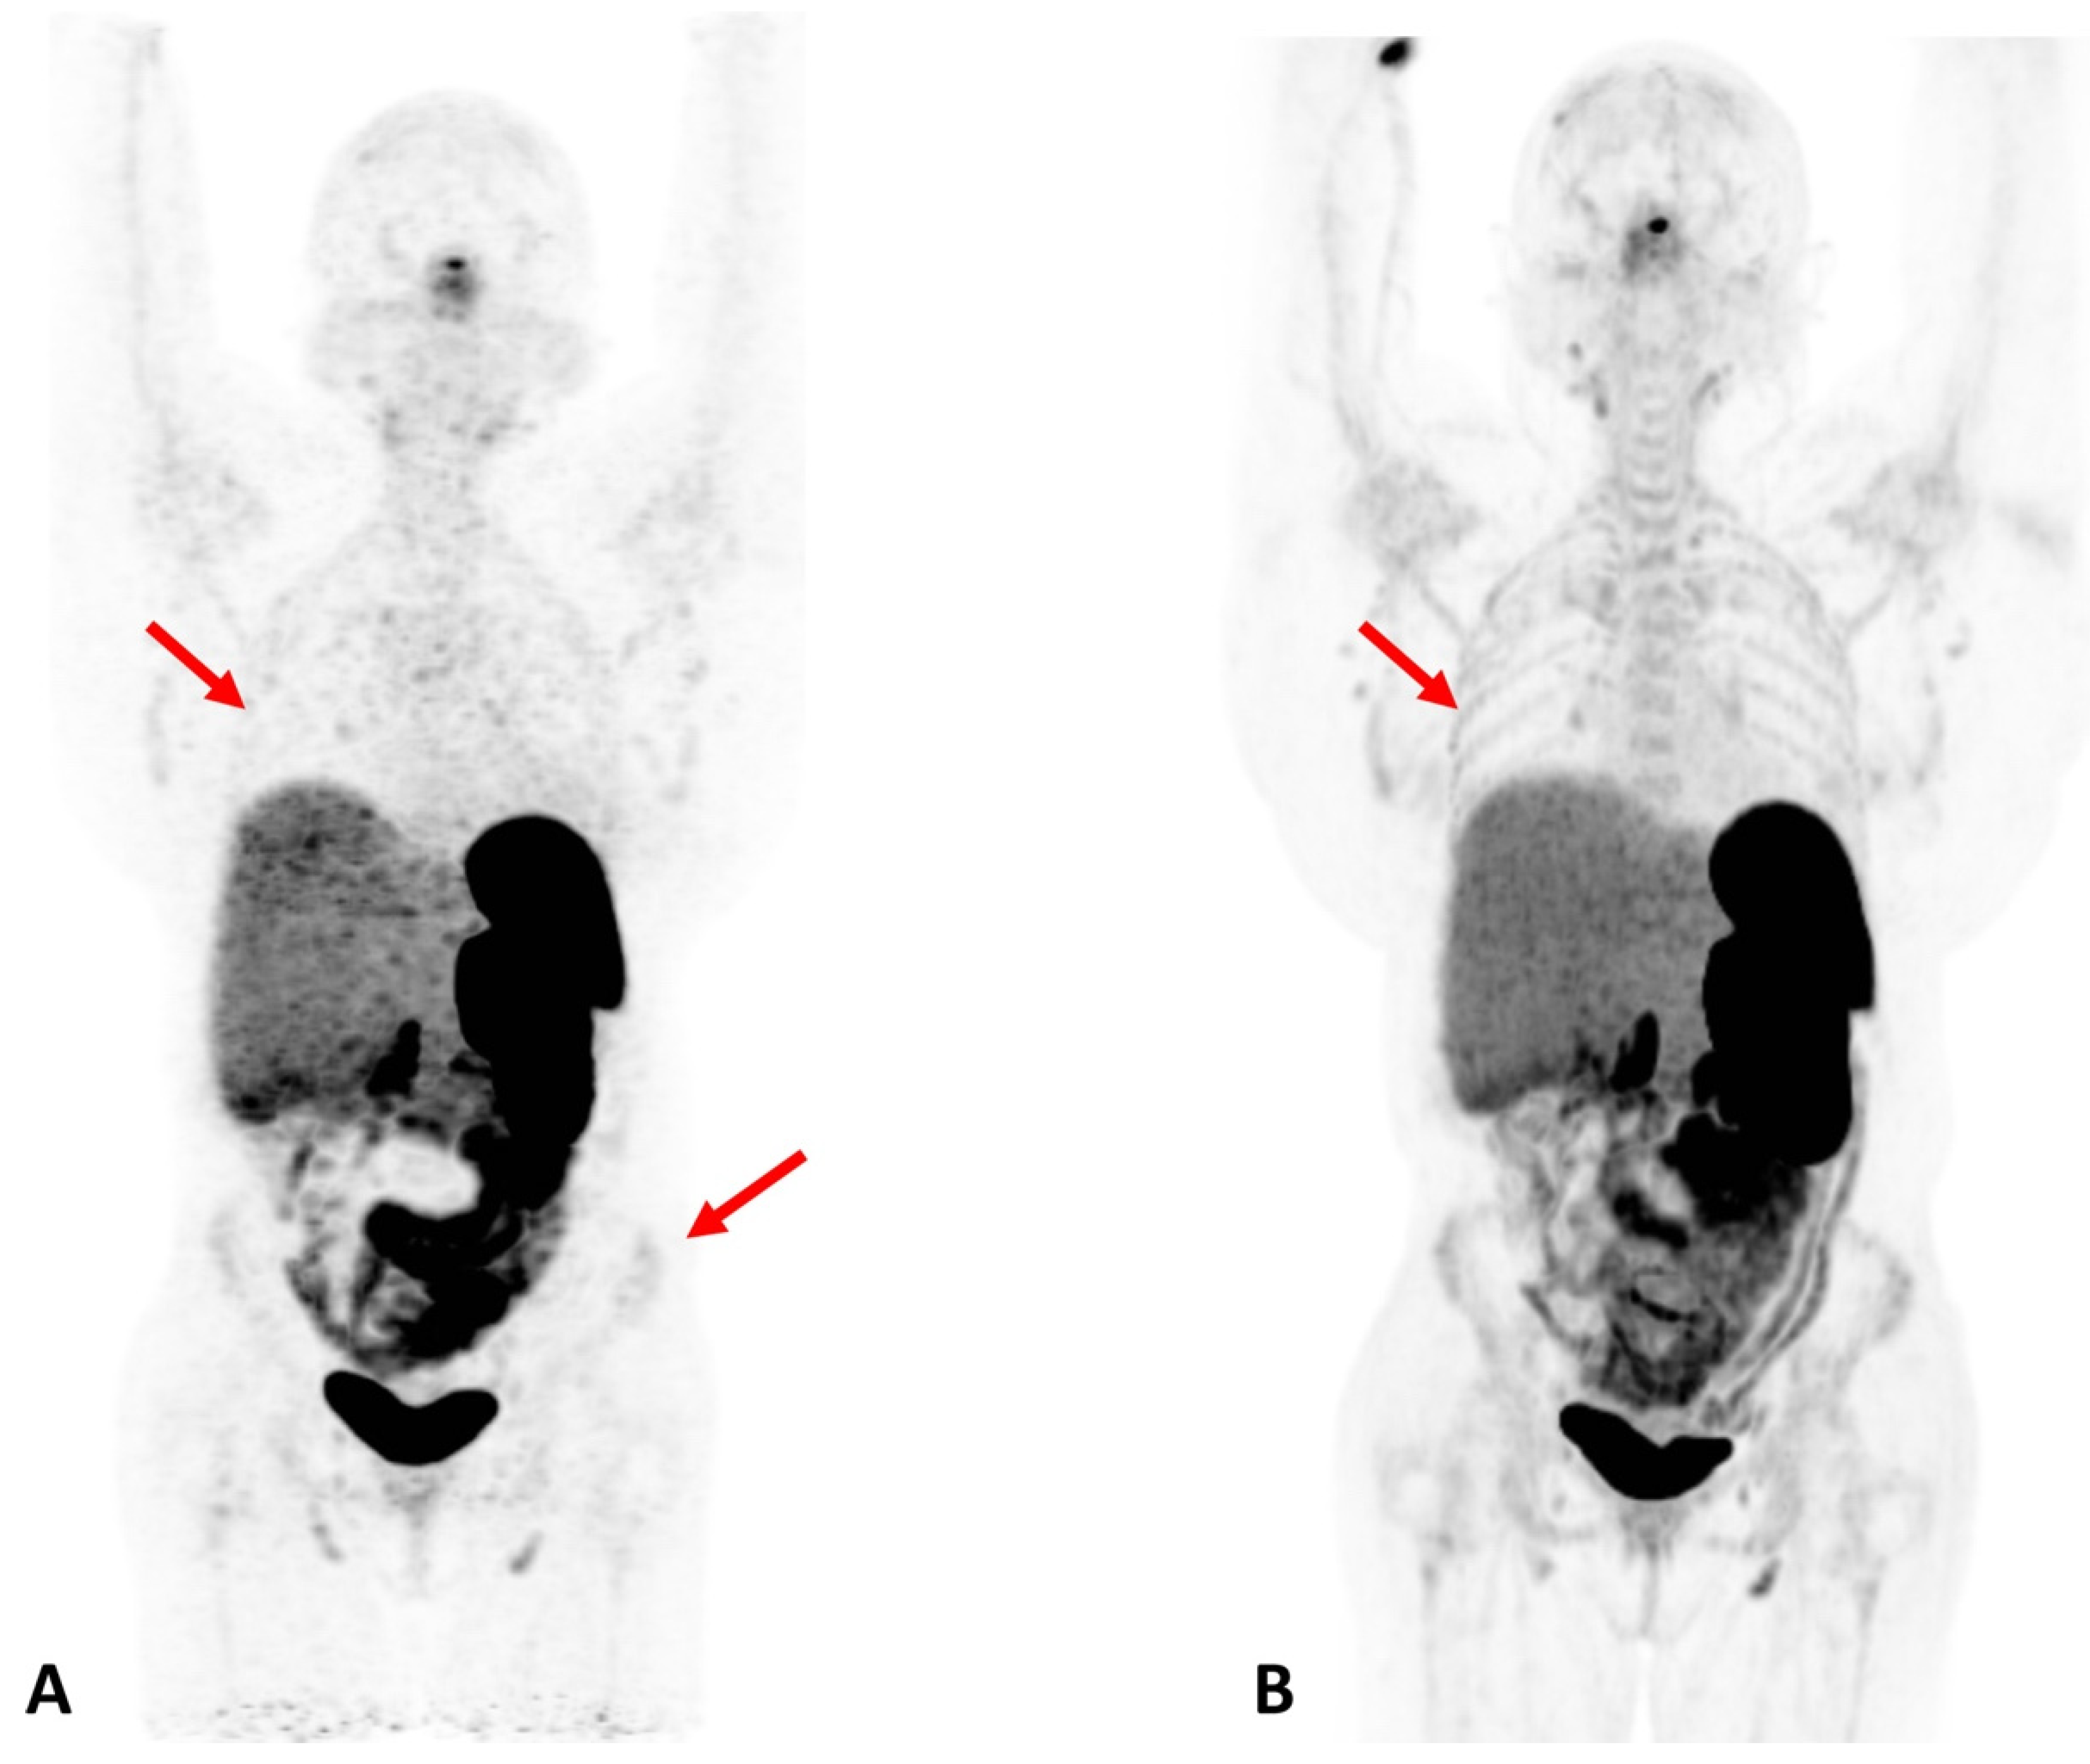

Obesity and metabolic syndromes: Total-body PET imaging coupled with various metabolic tracers and advanced modeling techniques has great potential in the field of metabolic disorders. These techniques can enable both clinicians and researchers to investigate the pathophysiology of obesity-related metabolic disorders, and therefore contribute to the development of targeted interventions [22]. In addition, imaging multiple organs simultaneously can shed light upon the role of different organs and tissues (white and brown fat tissue, skeletal muscles, lower gastrointestinal (GI) tract, central nervous system (CNS), etc.) in these diseases. Such metabolic information can help elucidate targeted strategies for the diagnosis and treatment of metabolic disorders. Figure 4 exemplifies the enhanced organ/bone visualization associated with total-body PET scanning [23].

Figure 4.

Patient with Cushing Syndrome post bilateral adrenalectomy. A dose of 167 MBq of 68Ga DOTATATE was injected, and a 20-min scan was performed after 60 min of uptake. (A) Baseline scan obtained on a conventional PET/CT scanner; (B) 6-month follow-up scan obtained on a total-body scanner. In the total-body PET/CT image, background noise is lower and the signal higher, allowing for clearer visualization of the liver. In addition, the increased signal level on the total-body scanner results in new or better visualization of bone details (arrows). Reprinted with permission from Ref. [23]. Copyright 2020 Elsevier.